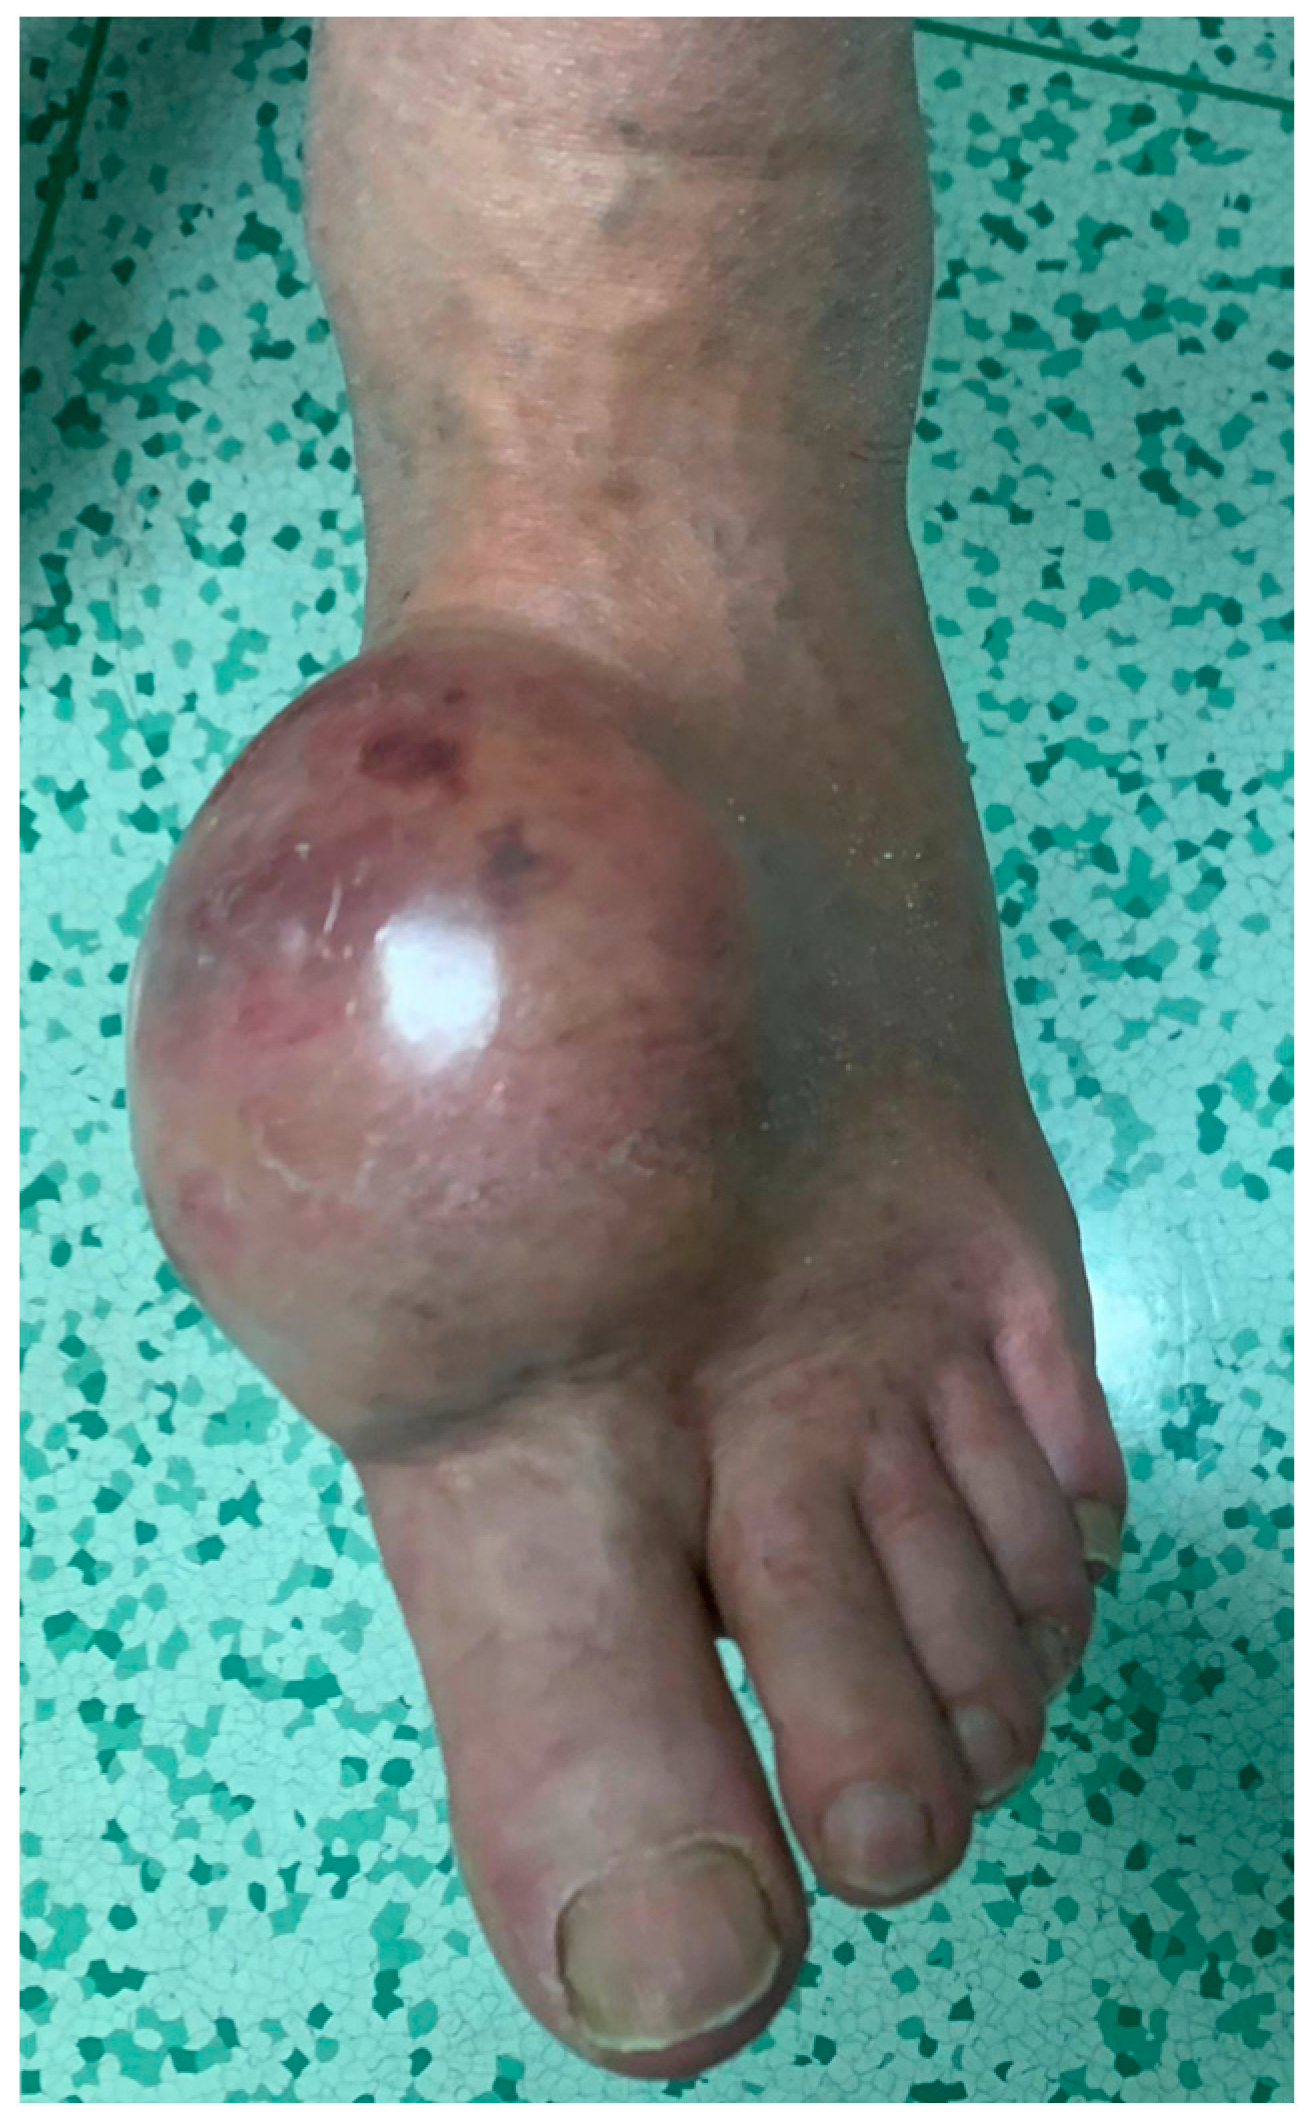

4.1. Melanoma